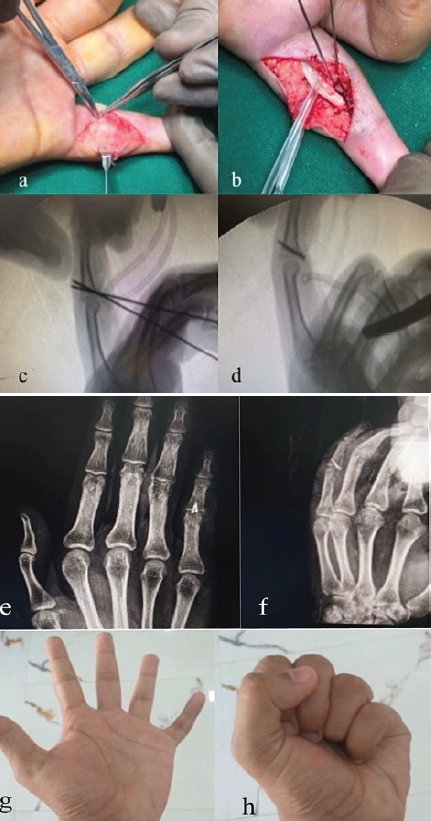

A 28-year-old male presented with a volar lip fracture of the middle phalanx of the left little finger, 20 days after injury. The fracture was managed with mini-screw fixation using a volar approach. Postoperatively, the patient was discharged with a dorsal splint applied in wrist extension with flexion at the metacarpophalangeal (MCP), PIP, and distal interphalangeal (DIP) joints, allowing full flexion with extension block for 2 weeks. After suture removal at 2 weeks, mobilization was initiated with strapping, and on follow-up, the patient achieved a post-operative ROM of 20–90° at the PIP joint (Fig. 1, 2).

Figure 2: Intra-Operative Clinical Pictures, C-Arm Shoots, Post Operative X-Rays & Follow Up ROM Clinical Picture (a) Volar Incision Taken Over Little Finger, (b) Flexor Tendon Retracted, K-wires placed, (c) C-arm shoot showing K-Wires, (d) C-arm shoot showing Mini-Screws, (e) Post-Operative X-Ray Left Hand AP View, (f) Post-Operative X-Ray Left Hand Oblique View, (g) 6 weeks Follow Up Image showing Finger Extension, (h) 6 weeks Follow Up Image showing Finger Flexion